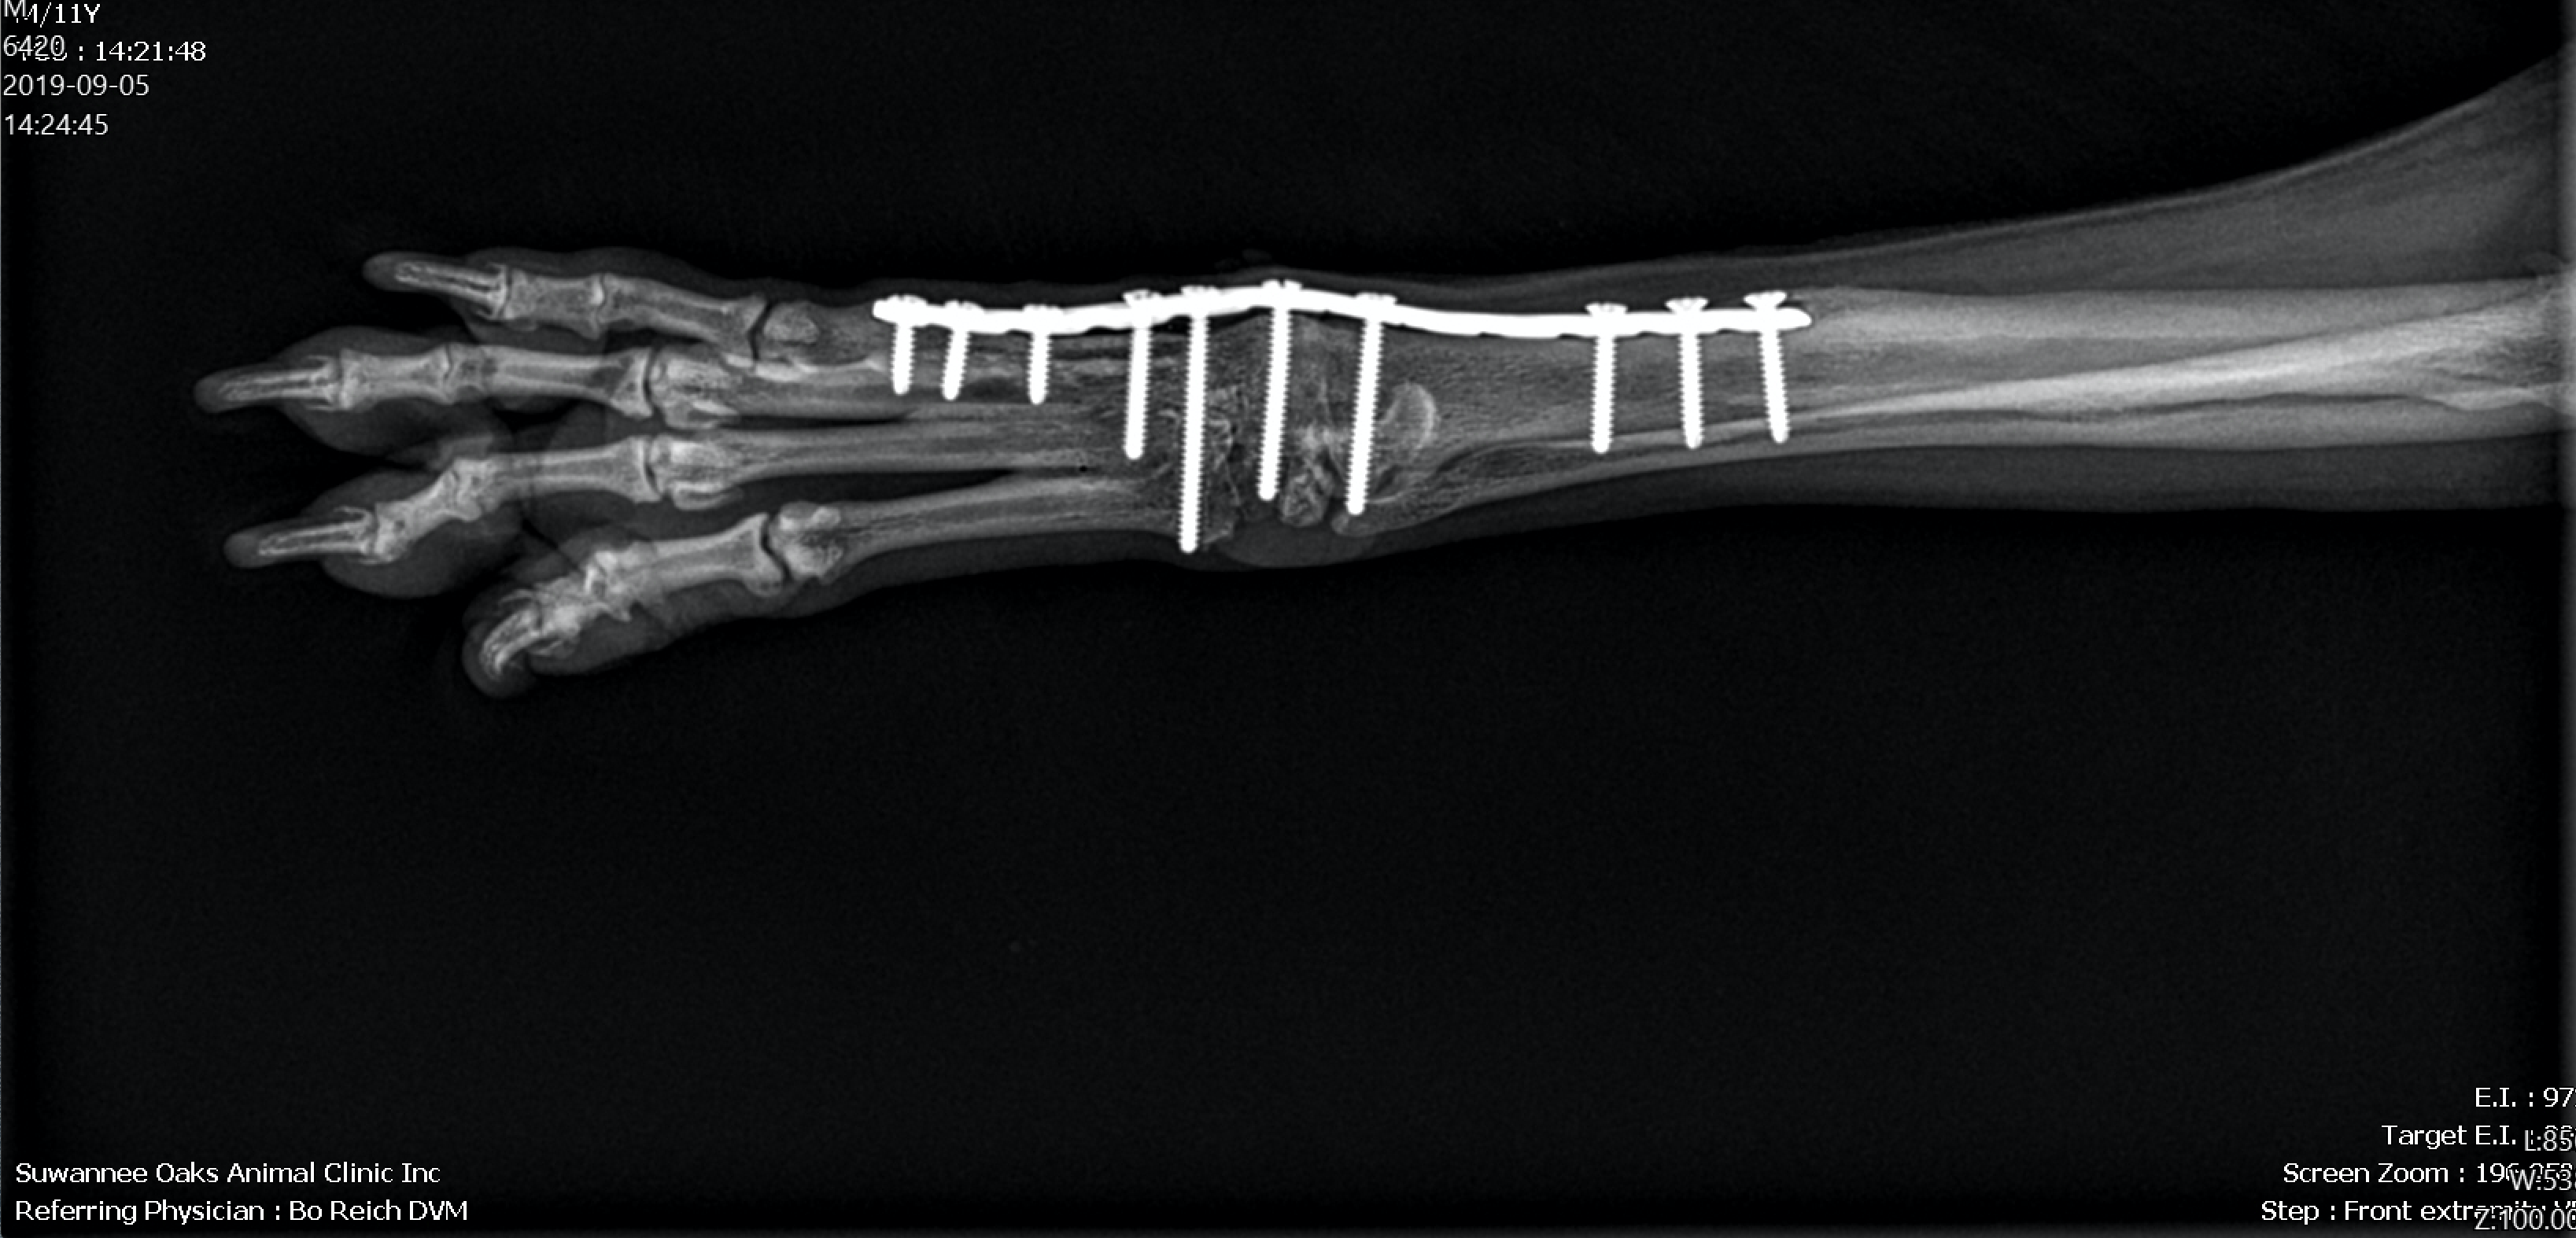

We have state of the art digital radiographic equipment that allows us to provide high quality imaging. This helps us diagnose a variety of conditions in dogs and cats. These images can be quickly sent to board-certified radiologists in selected cases for consultation when necessary.